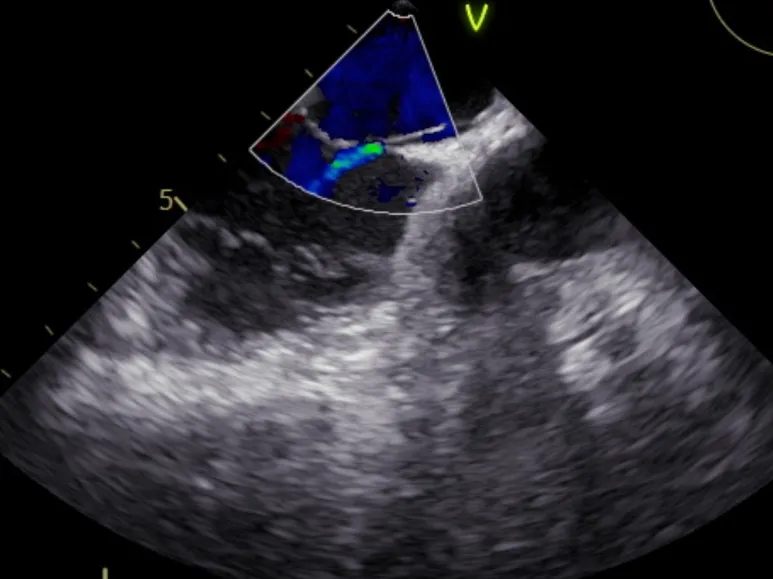

经食道超声

房间隔卵圆瓣处呈裂隙样改变;

宽0.8-1.0mm,长7mm;

瓦氏动作后,左房侧开口1.4mm。